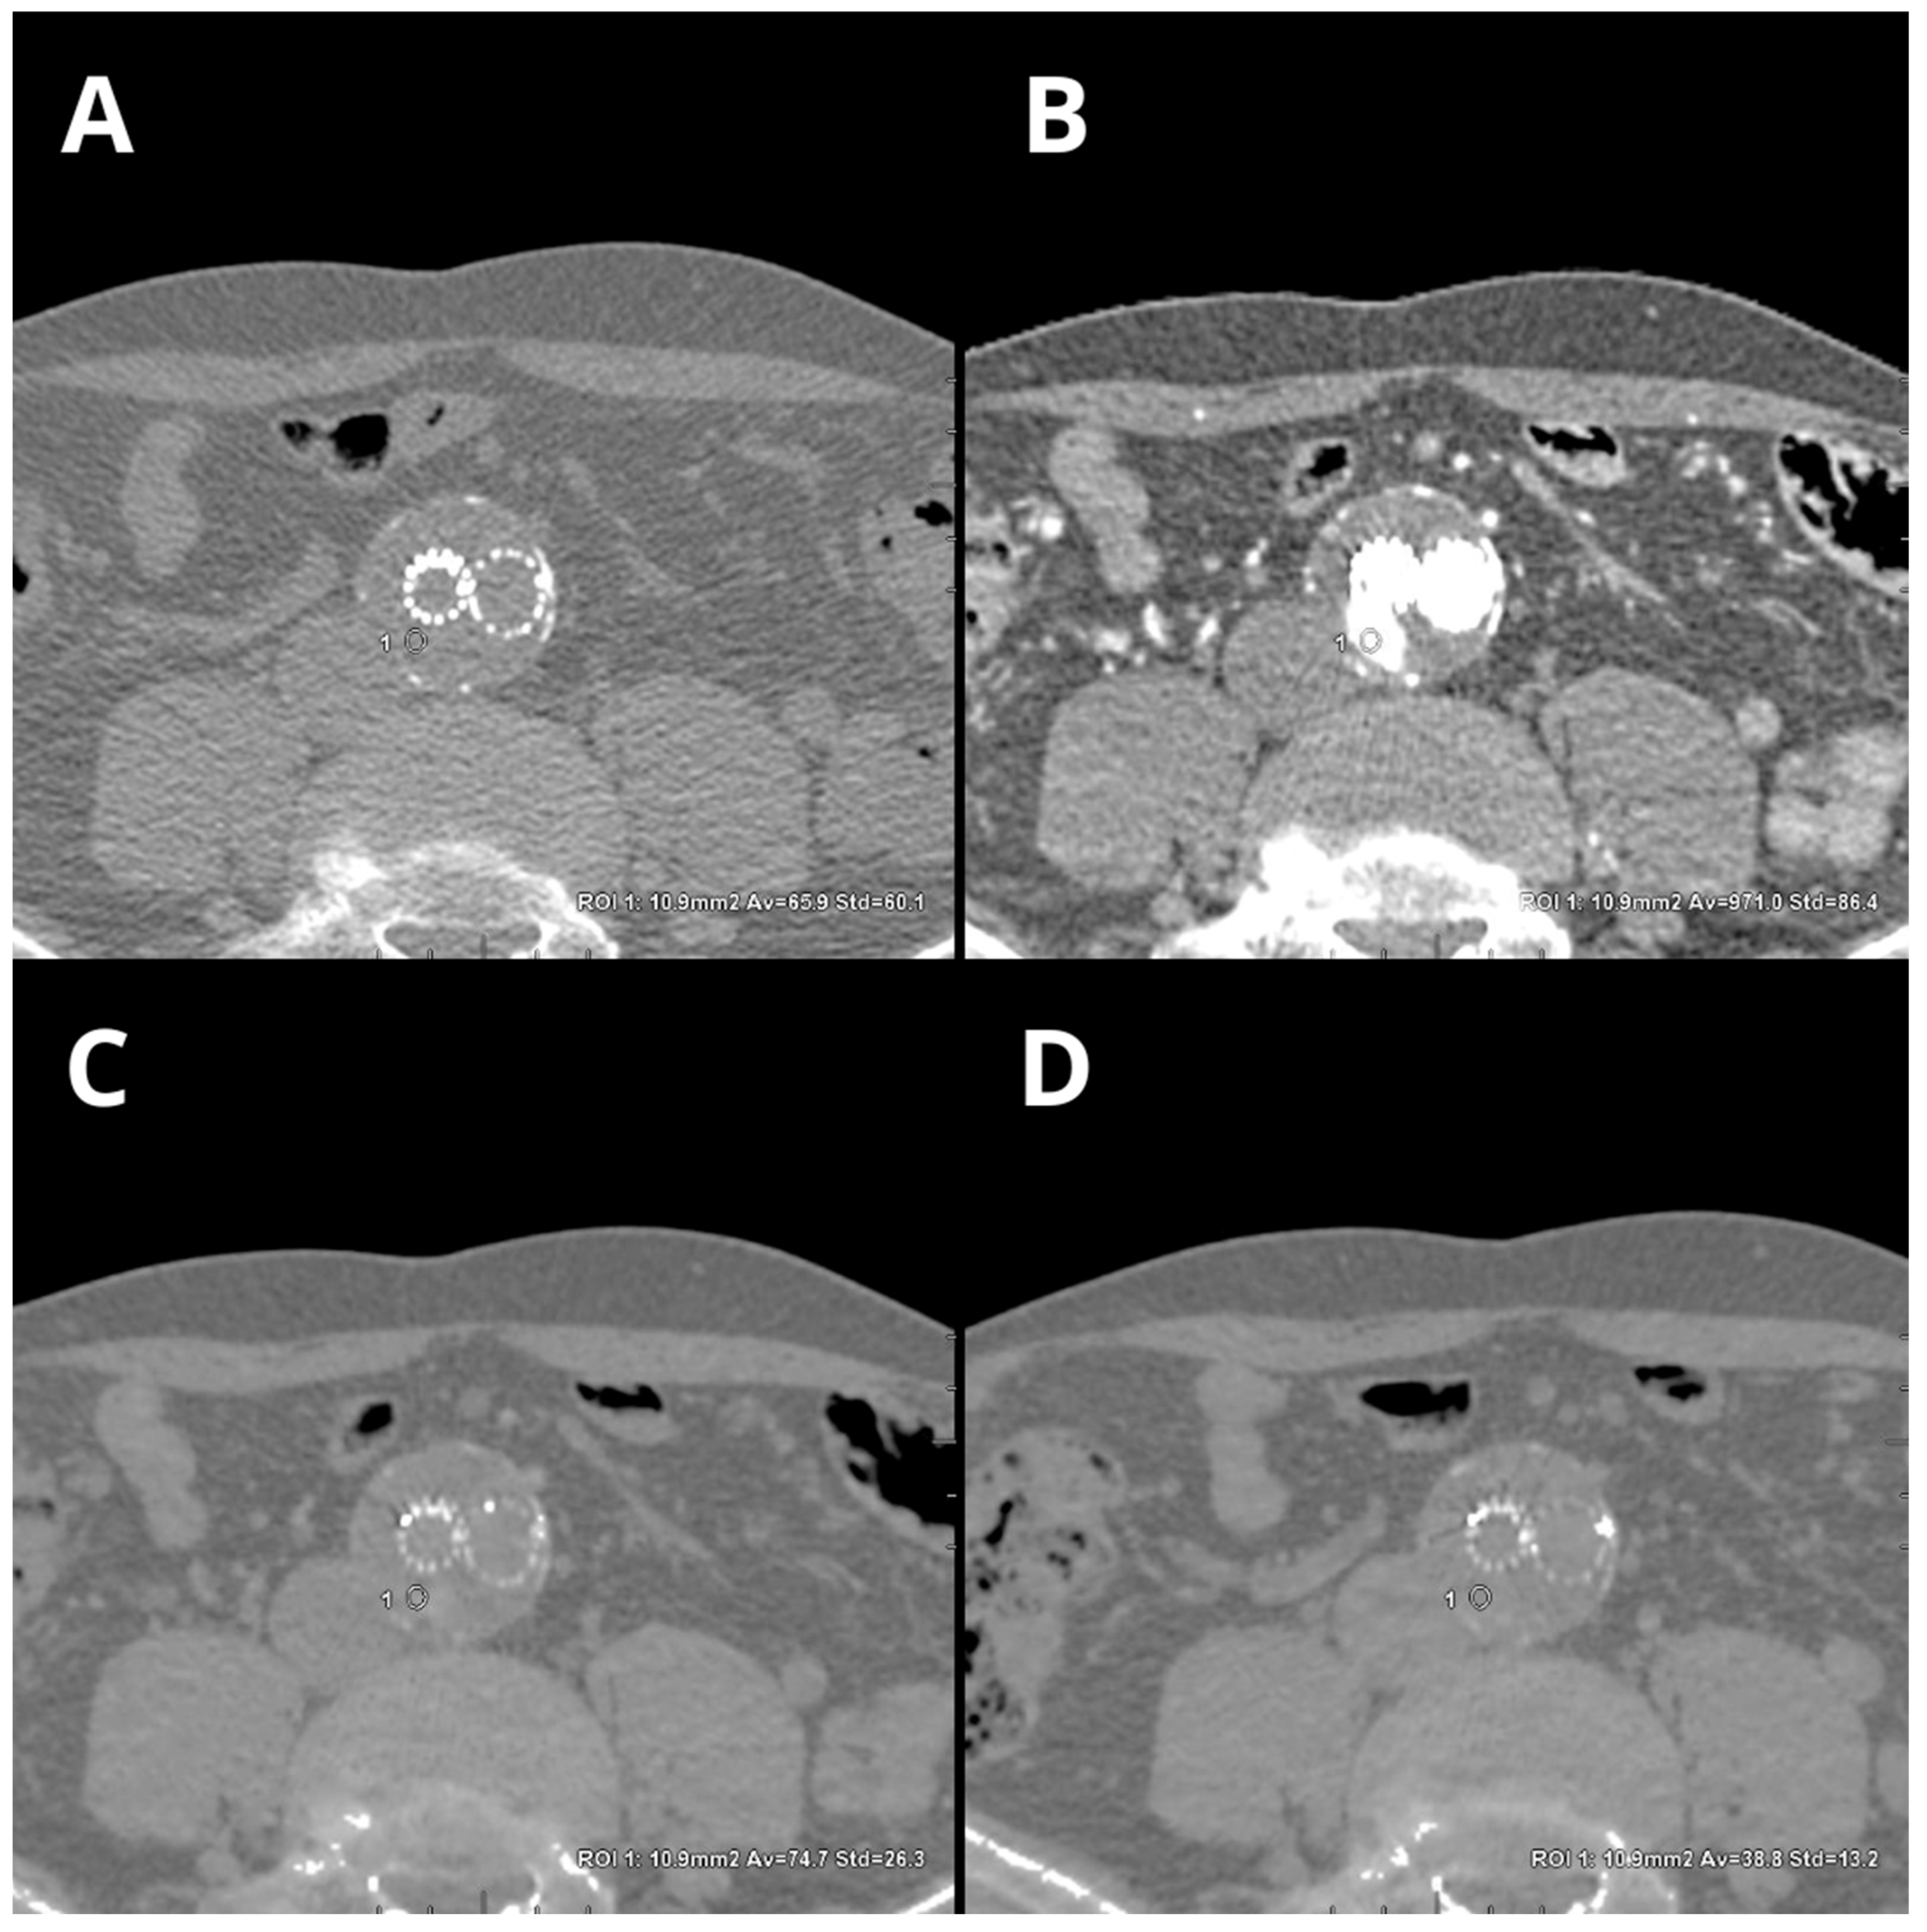

- Kazimierczak, W.; Kazimierczak, N.; Lemanowicz, A.; Nowak, E.; Migdalski, A.; Jawien, A.; Jankowski, T.; Serafin, Z. Improved Detection of Endoleaks in Virtual Monoenergetic Images in Dual-Energy CT Angiography Following EVAR. Acad. Radiol. 2023, 30, 2813–2824. [Google Scholar] [CrossRef]

- Maturen, K.E.; Kaza, R.K.; Liu, P.S.; Quint, L.E.; Khalatbari, S.H.; Platt, J.F. “Sweet spot” for endoleak detection: Optimizing contrast to noise using low kev reconstructions from fast-switch kVp dual-energy CT. J. Comput. Assist. Tomogr. 2012, 36, 83–87. [Google Scholar] [CrossRef] [PubMed]

- Martin, S.S.; Wichmann, J.L.; Weyer, H.; Scholtz, J.-E.; Leithner, D.; Spandorfer, A.; Bodelle, B.; Jacobi, V.; Vogl, T.J.; Albrecht, M.H. Endoleaks after endovascular aortic aneurysm repair: Improved detection with noise-optimized virtual monoenergetic dual-energy CT. Eur. J. Radiol. 2017, 94, 125–132. [Google Scholar] [CrossRef]

- Skawran, S.; Angst, F.; Blüthgen, C.; Eberhard, M.; Kälin, P.; Kobe, A.; Nagy, D.; Szucs-Farkas, Z.; Alkadhi, H.; Euler, A. Dual-Energy Low-keV or Single-Energy Low-kV CT for Endoleak Detection? Investig. Radiol. 2020, 55, 45–52. [Google Scholar] [CrossRef] [PubMed]